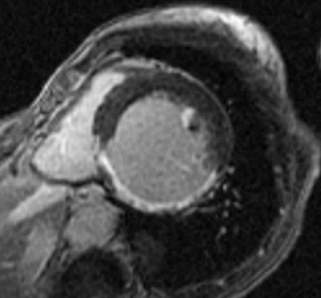

Fig.1., 2.: Hypertrophic obstructive cardiomyopathy: Longitudinal and short axis slices of delayed enhancement of contrast material in the heart: pathologic enhancement is visible in the myocardium in the asymmetrically thickened left ventricular wall, referring to a degenerative-fibrotic process.